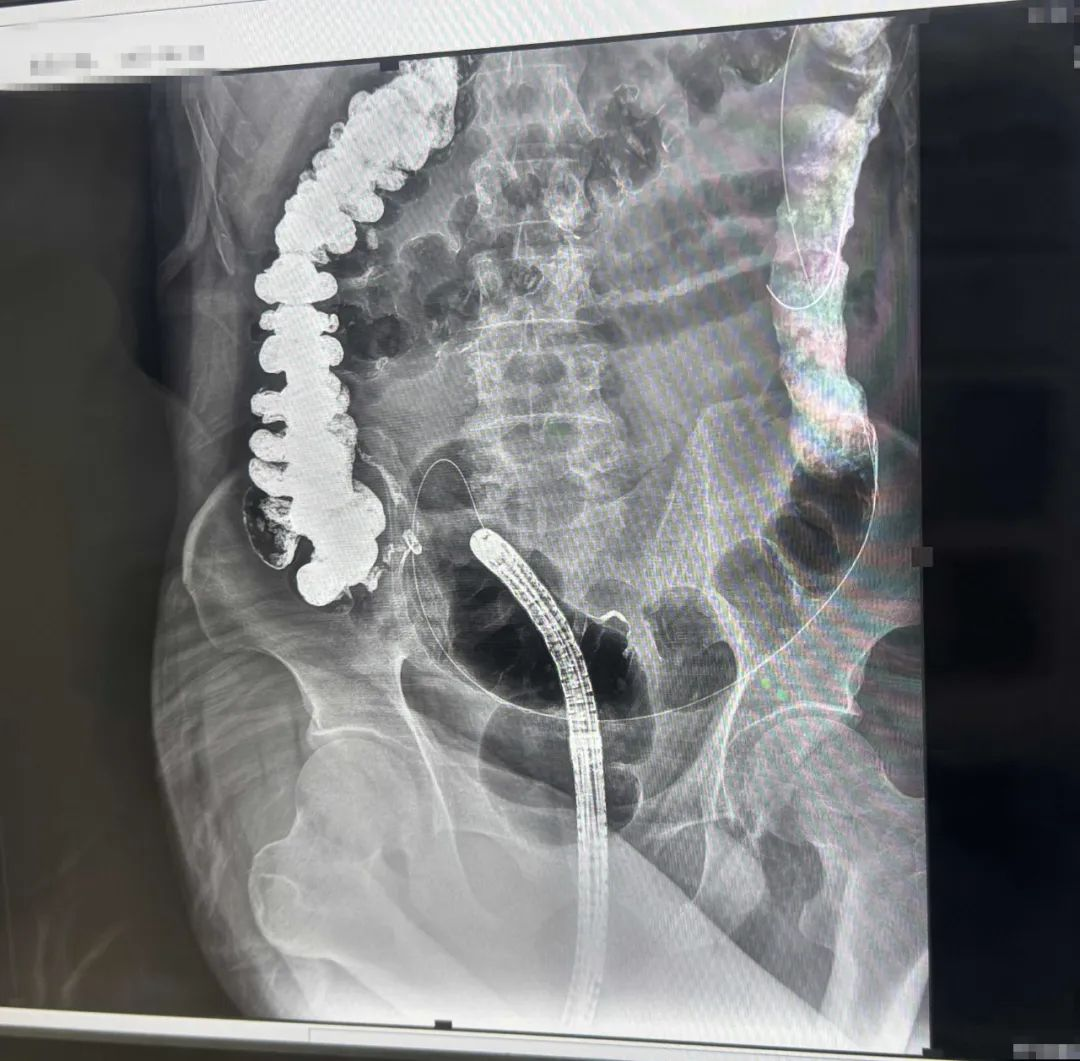

▲导丝越过肿瘤梗阻段X线

诊疗思路决定治疗入路,治疗入路决定病情出路。就这样,消化内科团队在李捷壮、刘烈辉主任的指导下,由省医派驻专家、消化内科副主任郑中文,消化内科主治医师黄懿波担任主刀,高宝娟护士长、张秋娟组长的内镜护理保障,于近日成功实施河源首例急诊内镜下肠道支架植入术,手术顺利,耗时约50分钟,患者全程体验感良好,无明显痛苦不适,术后患者立马排出大量粪便,腹痛腹胀随之缓解,顺利打通堵塞肠管,避免传统开腹造瘘的痛苦,为后续根治手术赢得宝贵时间。

精准定位难题攻克:结合窄带成像(NBI)与X线双透视,精确定位直乙交界狭窄段(距肛缘12至15cm高危区)。

革新系统技术:引入直径26mm的可回收覆膜支架,精准攻克传统金属支架易移位的难题。